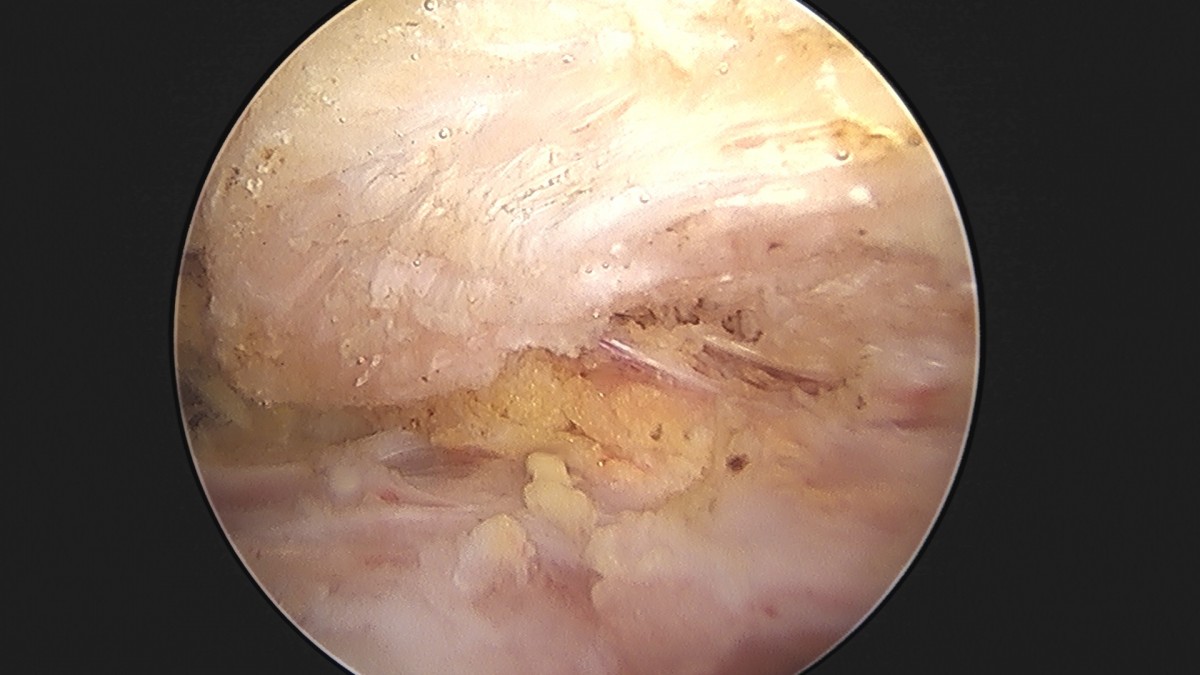

이재상원장님 어깨 견봉하 감압술 및 석회 제거술 이형O 환자

작성자 최고관리자 댓글 0건 조회 746회 작성일 25-09-16 15:40